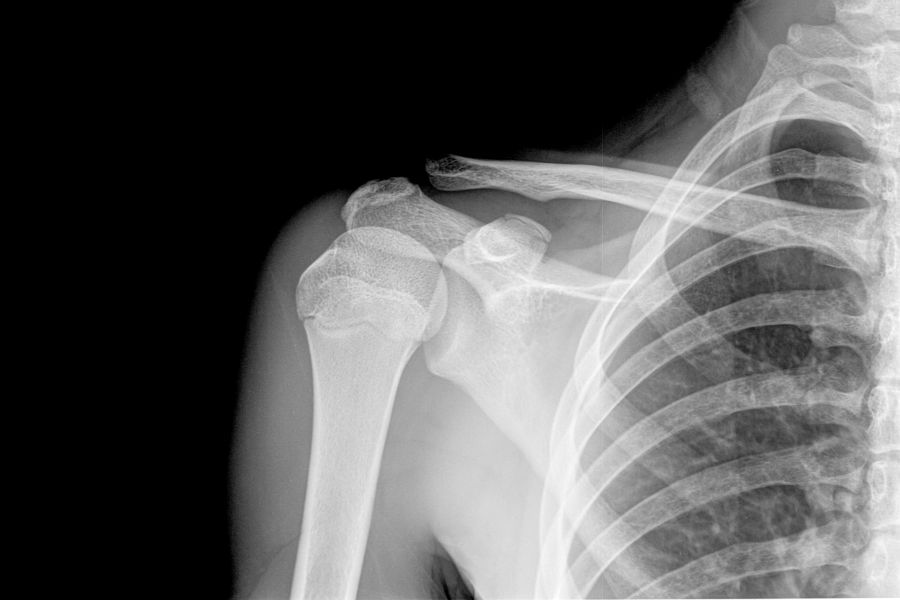

Aby potwierdzić wystąpienie chrzęstniaka i określić stopień zaawansowania zmiany, należy przeprowadzić odpowiednie badania obrazowe: zdjęcie rentgenowskie (RTG), tomografię komputerową (TK) lub rezonans magnetyczny (MRI). O łagodnym charakterze zmiany świadczy brak oznak zniszczeń na otaczających tkankach oraz powtarzalne wyniki badań obrazowych, wykonywanych w równych odstępach czasu. Ostateczne rozpoznanie można uzyskać po przeprowadzeniu badania histopatologicznego.